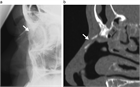

1. X線画像検査で大方の骨折は診断が可能である。

1. 受傷後7~10日程度であれば、局所麻酔下にAsch鼻骨整復鉗子などを用いて非観血的に徒手整復する。